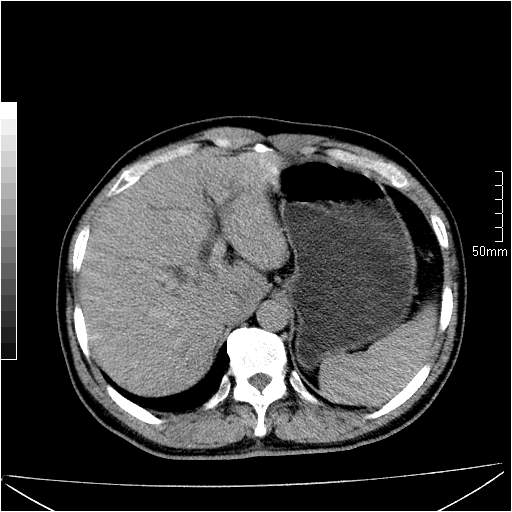

男性,54岁,皮肤黄染,搔痒一周余.b超示肝左叶回声异常.初步诊断1胆总管下段结石2胆囊结石伴慢性胆囊炎请各位战友帮忙看一下肝脏多发低密度如何解释恰当.增强效果不是很好.请大家见谅.

胆总管结石,致肝内外胆管增粗,胆内低密度影建议增强扫描

首先,胆总管下端结石梗阻伴肝内胆管扩张可确定。

既然做了增强,为什么光提供延时期片子,肝动静脉期肝右叶前下段病灶增强如何?另外胆囊壁增厚,欠规整,内密度不均,与肝右叶病灶分界不清,增强表现怎样?肝内胆管轻度扩张,胆总管扩张,但未见明显结石影,也应提供增强早期图像才好鉴别扩张原因。片子较清,但不够完整,暂考虑1.胆囊癌肝局部浸润,或肝癌胆囊侵犯,2.胆总管下端或胰头钩突部占位。总之本人看不明白,请高手画图指示,先谢了!

由于胆囊窝内结构显示不清,肝脏病灶又邻近胆囊窝首先考虑胆囊癌肝受侵犯。而后因肝脏病灶强化有渐进改变,且相邻胆管扩张,故考虑肝胆管细胞癌待排。

左肝胆管细胞癌。

胆总管下端结石。